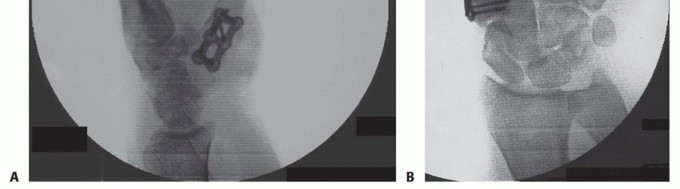

POSITIONING AND FIXATION

TECH FIG 3 • A. A six-hole plate is applied across the CMC joint. B. Two screws have been placed through the plate into the trapezium. C. Plate being applied onto the thumb CMC. D. Distal radius bone graft being packed into the CMC joint. Distal radius bone graft is then packed into the fusion site (TECH FIG 3D).At this time, final assessment of clinical alignment and fluoroscopic evaluation (position, bony contact, hardware placement/screw length) are performed (see FIG 2A,B).Irrigate the wound lightly with saline. Close the capsule with a nonabsorbable suture (3-0 Ethibond), repeat irrigation, and deflate the tourniquet to confirm hemostasis as the radial artery and venae comitantes are within the operative field. Close the skin with 4-0 nylon horizontal mattress sutures.If mild thumb MCP joint hyperextension is noted at this juncture, pin the MCP joint in 20 degrees of flexion with a single 0.045 Kirschner wire or consider a volar capsulodesis. In our experience, correction of the fixed flexion and adduction of the thumb metacarpal often improves MCP position with pinch so that operative intervention at the MCP joint is infrequent.Apply soft sterile dressings and a well-padded short-arm thumb spica splint.